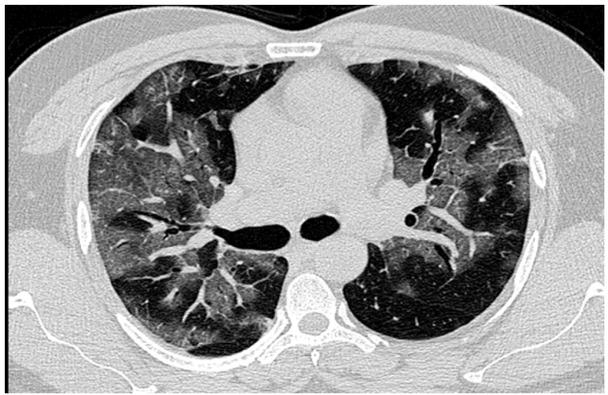

Fig. 1A